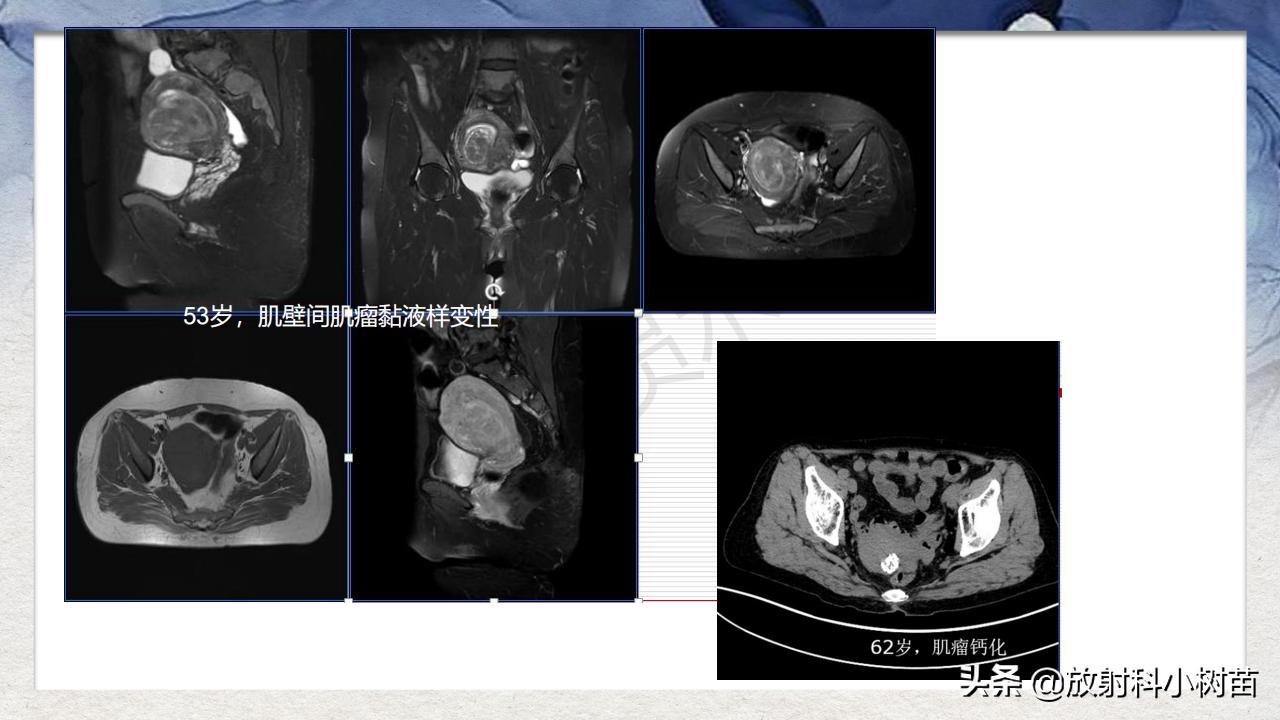

子宫体:肌层?(腺肌症,肌瘤,肉瘤),内膜?(增生,息肉、内膜癌)